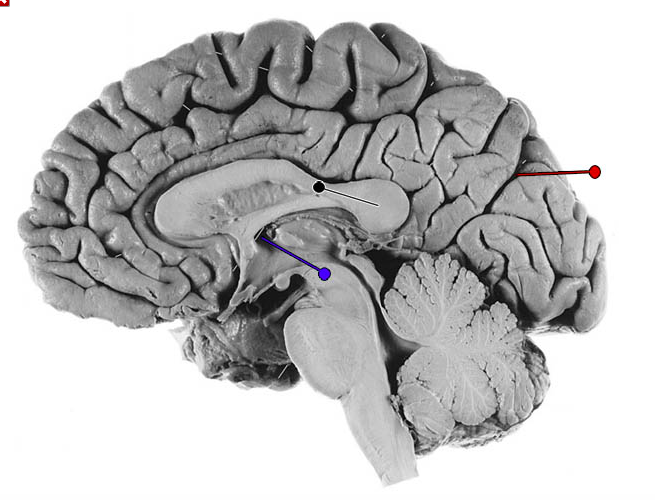

What is the structure indicated by the black pin?

?

What fibres is the structure marked by the black pin made up of?

Commisural fibres